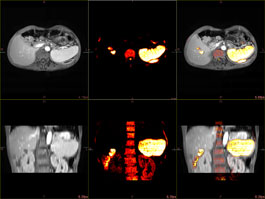

FUSION VIEWER

The PET/CT Fusion protocol provides flexible and simple image overlay analysis. Standard Uptake Value calculations are enabled with ROIs and VOIs.

MULTI-MODALITY FUSION

Up to four different series from different phases or even modalities can be layered using varied opacity profiles.